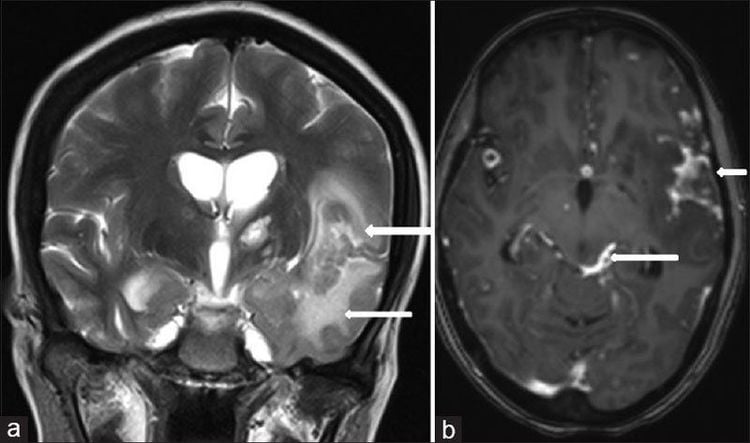

Lao màng não là trường hợp hiếm gặp ở bệnh nhân nhiễm vi khuẩn Mycobacterium Tuberculosis (MTB) nhưng có nguy cơ tử vong cao nhất trong các loại bệnh lao hiện nay. Nguy hiểm hơn, dấu hiệu lao màng não thường tương tự với nhiều bệnh lý khác khiến việc phát hiện và điều trị kịp thời gặp nhiều khó khăn.

Trong các loại bệnh lao thì lao màng não chỉ chiếm 5% trong tổng số các ca bệnh lao ở nước ta. Tuy nhiên, đây lại là thể nguy hiểm nhất và có tiên lượng nặng nếu không phát hiện và điều trị kịp thời.

Mặc dù, lao màng não triệu chứng rất phong phú nhưng khá giống với nhiều bệnh về não khác nhau như u não, xuất huyết não, viêm màng não mủ... Do đó, việc chẩn đoán lâm sàng thường gặp nhiều khó khăn, thậm chí là chẩn đoán nhầm khiến việc điều trị ban đầu sai sót. Bên cạnh đó, việc xác định chẩn đoán cũng gặp nhiều khó khăn bởi tỷ lệ báo âm tính giả lên đến 50% khiến việc điều trị chậm trễ, tỷ lệ tử vong tăng cao.